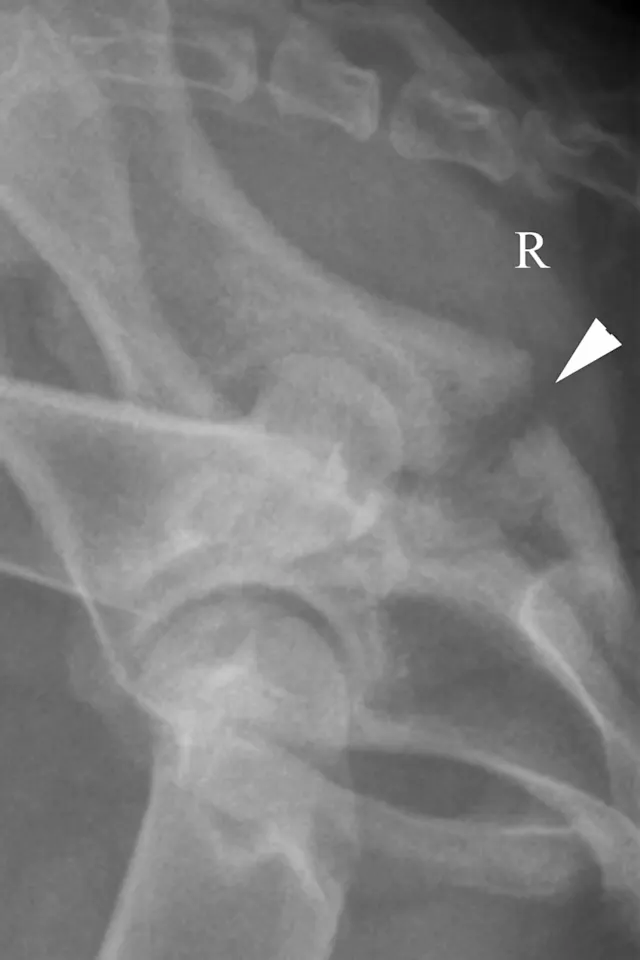

Due to the superimposition of the opposite hemipelvis and proximal femurs on the lateral radiograph, it can be useful to obtain oblique radiographs by rotating the pelvis slightly when the dog is in lateral recumbency. This is done by pushing the limb on the side with suspected pathology dorsally (away from the holder) and pulling the opposite limb/pelvis ventrally (toward the holder), as shown in Figure 4A (white arrows). Dorsal acetabular pathology is best seen if the acetabulum in question is positioned dorsally relative to the normal side. In Figure 4B, an indistinct lucent area is noted just caudal to the acetabulum. The oblique radiograph (Figure 4C), with the right hemipelvis dorsal, clearly shows that the fracture (white arrowhead) does not involve the acetabulum.